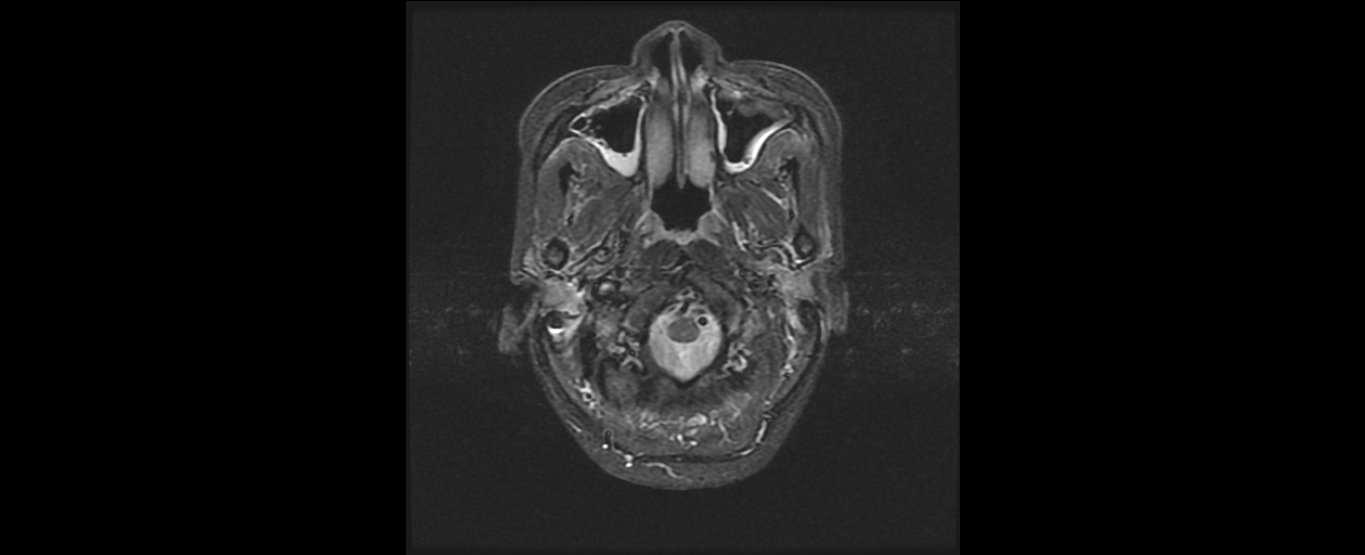

患者韦某某,女,37岁,2016年8月诊断为:鼻咽非角化未分化型癌(T2N2M0 III期),诱导化疗后行鼻咽癌根治性调强放疗,同期顺铂化疗,放疗结束后案辅助化疗。治疗结束复查见患者鼻咽肿物及颈部淋巴结均消退,疗效良好,目前随访1年患者各项检查指标完全恢复正常,已经恢复正常生活和工作。

放疗前鼻咽部MRI